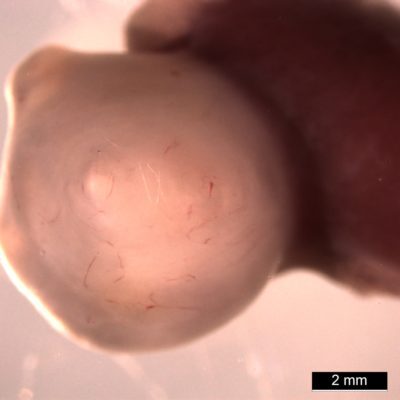

为了进一步推动类器官的发展,在发展的30天左右,研究小组将其移植到小鼠体内。在那里,它们有了血流和更多的空间,这些器官组织比它们通常在细胞培养中的体积大了一千倍。它们甚至还产生了其他一直缺乏的东西如布鲁纳氏腺,它能分泌一种保护肠道上部免受胃酸影响的碱性溶液。